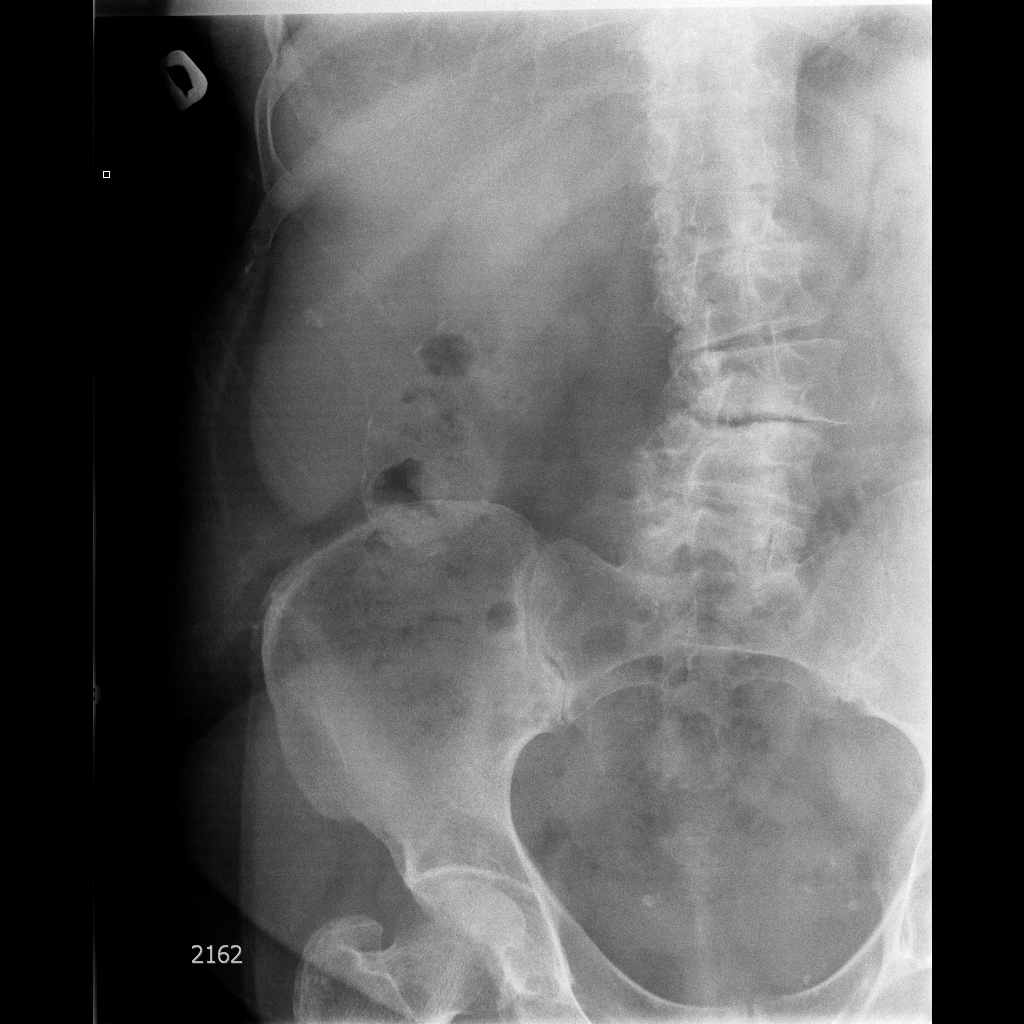

Фарфоровый желчный пузырь (Porcelain gallbladder)

Женщина средних лет без жалоб на здоровье.

Еще случай.

Бабушка из отделения сестринского ухода, без жалоб на боли в животе. Лаб. анализы не изменены.